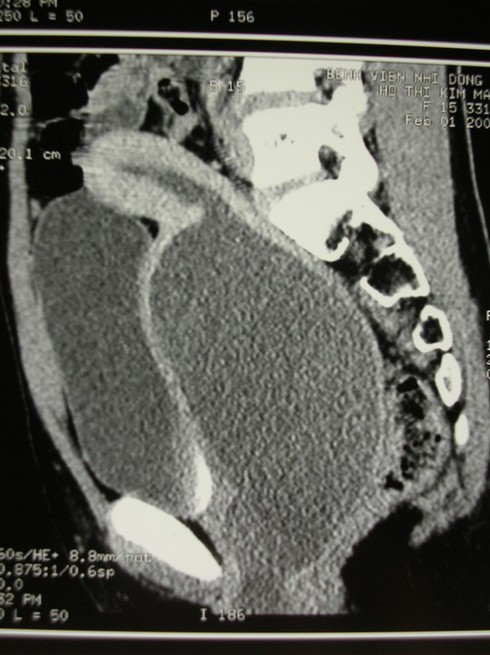

Giữa tháng 12, người nhà đưa bé vào một bệnh viện tuyến quận trong tình trạng đau bụng dữ dội, bụng phình to và bí tiểu. Qua thăm khám, các bác sĩ chẩn đoán màng trinh của bé H. không có lỗ để thoát máu kinh và dịch ra bên ngoài. Vì thế, bé H. được phẫu thuật rạch mép màng trinh. Tuy nhiên, sau khi phẫu thuật, bé H. vẫn đau bụng dưới và bí tiểu phải chuyển lên Bệnh viện Nhi Đồng 2.

Tại Bệnh viện Nhi Đồng 2, bé H. đã được các bác sĩ chẩn đoán ứ máu kinh trong tử cung âm đạo nhưng do nguyên nhân là bất sản âm đạo. Bé đã được phẫu thuật cấp cứu nhằm giải thoát lượng máu kinh ứ đọng trong nhiều tháng liền và tái tạo lại âm đạo.